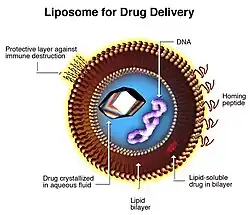

Lipid-based nanoparticles

Lipid-based nanoparticles (LNP) can deliver molecules with low toxicity and controlled release. Liposomes, solid lipid nanoparticles (SLN), nanostructured lipid carriers (NLC), and nanoemulsions are examples.

Liposomes are made up of phospholipids forming spherical vesicles. This property enables liposomes to exhibit high biocompatibility and biodegradability. Studies report potential application of liposomes to treat brain diseases due to increased retention and absorption in nasal cavity, and high brain biodistribution.[37] A previous study developed a cationic liposome loaded with mRNA and green fluorescent protein (GFP). Intranasal delivery of this formulation in murine models demonstrated high brain biodistribution and expression of mRNA-GFP.[38]